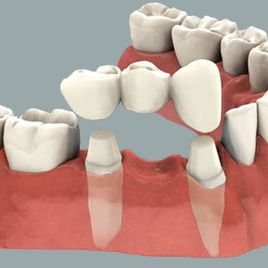

PUENTE FIJO

Cubre completamente uno o varios dientes pilares que sostienen los dientes pónticos en los espacios faltantes. Se utiliza para remplazar el espacio de una o varias piezas dentales.